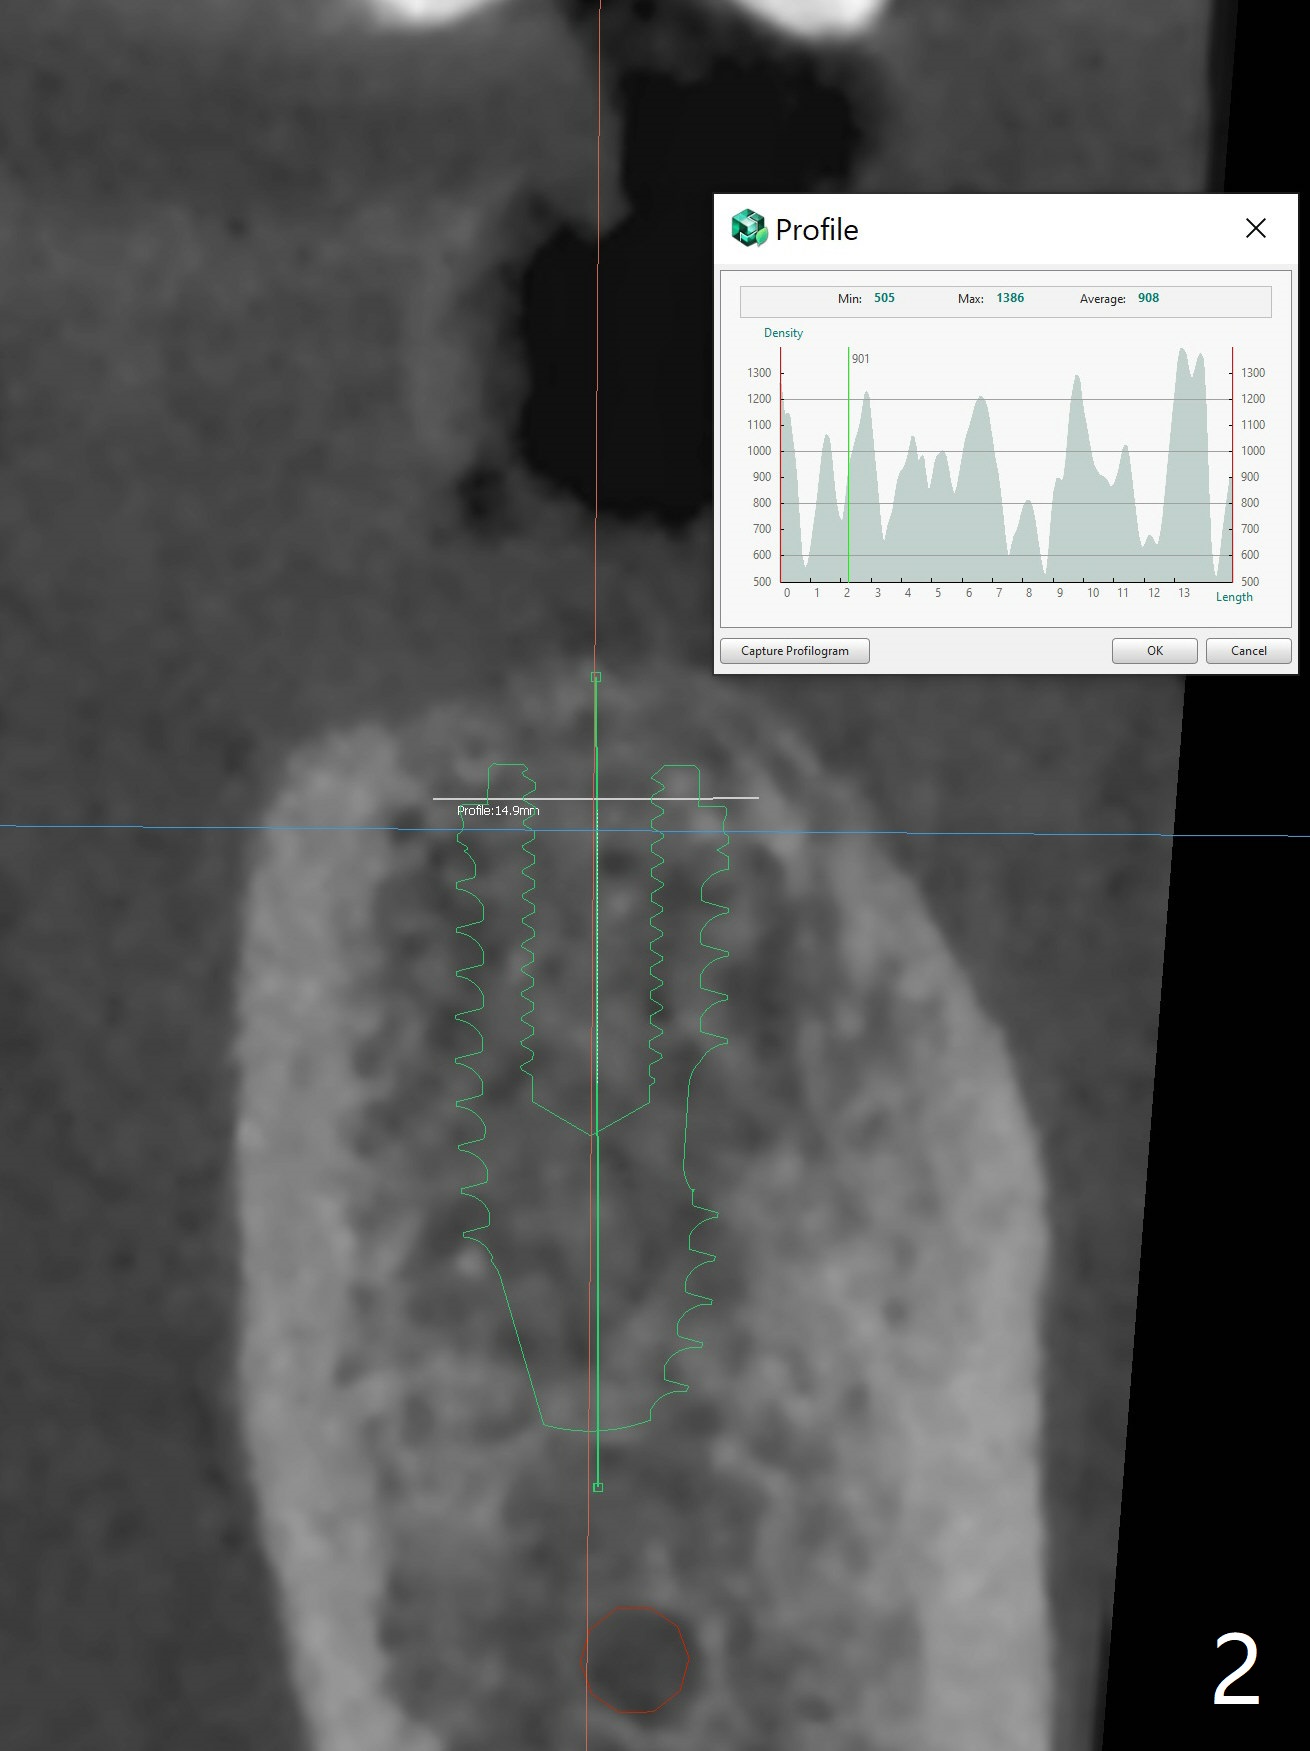

55岁女失去左下6十八年,害怕治疗,但是害怕面部变形才下决心种植,牙槽嵴宽(图一),骨质密度偏高(图二)。完成5x10毫米钻洞,植入4.5x10毫米报废植体,判断张口度。如果病人张口有余地,加深钻洞